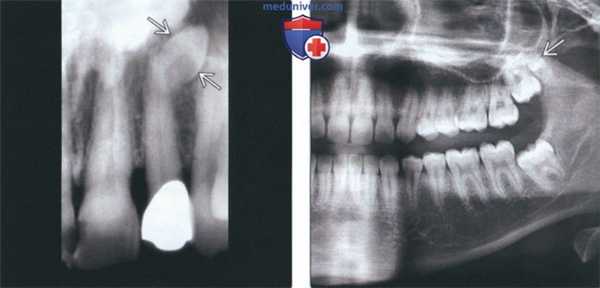

(Слева) На периапикальной рентгенограмме визуализируется маленький непрорезавшийся сверхкомплектный зуб (мезиоденс) рядом с боковым резцом.

(Справа) На панорамной рентгенограмме визуализируется сверхкомплектный (четвертый) моляр верхней челюсти, называемый также дистоденс или дистальный моляр. Дистоденс - второй наиболее часто встречающийся сверхкомплектный зуб после мезиоденс. Сверхкомплектные зубы могут быть изолированной находкой либо иметь связь с синдромом, например ключично-черепной дисплазией.

(Слева) На аксиальной трехмерной реконструкции верхней челюсти (КЛКТ) у пациента с ключично-черепной дисплазией визуализируются множественные непрорезавшиеся постоянные и сверхкомплектные зубы; коронки и корни некоторых из них имеют нетипичную форму.

(Справа) На панорамной реформатированной КЛКТ у этого же пациента определяется гипердонтия обеих челюстей. Обратите внимание на оставшиеся временные моляры и три формирующихся премоляра. У пациентов с ключично-черепной дисплазией может наблюдаться гипоплазия или отсутствие ключиц.